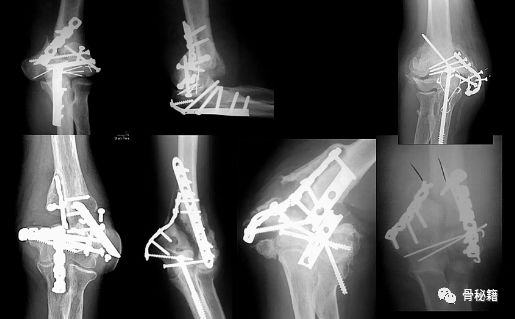

看看这些失败的case,肱骨远端不简单!

早期的AO技术

AO最早是90-90度钢板的派系,与平型钢板打的火热,后来没打过

1.钢板的形态没有特殊特定的,需要塑性预弯尤其在控制远端的骨折块的时候,钢板和螺钉的角度都必须十分讲究2. 对于滑车的固定只能应用最远端的拉力螺钉,与钢板不能连接3.这种固定在肱骨髁之间无法完成较好的骨折块之前的加压固定

所以对于这样固定的患者就面临一个问题,如果敢早期锻炼,就可能愈合不良,如果石膏固定时间长的话,肘关节就会僵硬

基于应用AO技术的话,固定要点1.一定要将钢板尽量往远端放,把远端骨块固定好2.髁间的固定一定要坚强,加压!3.尽量的坚强固定4.固定基础下早期功能锻炼